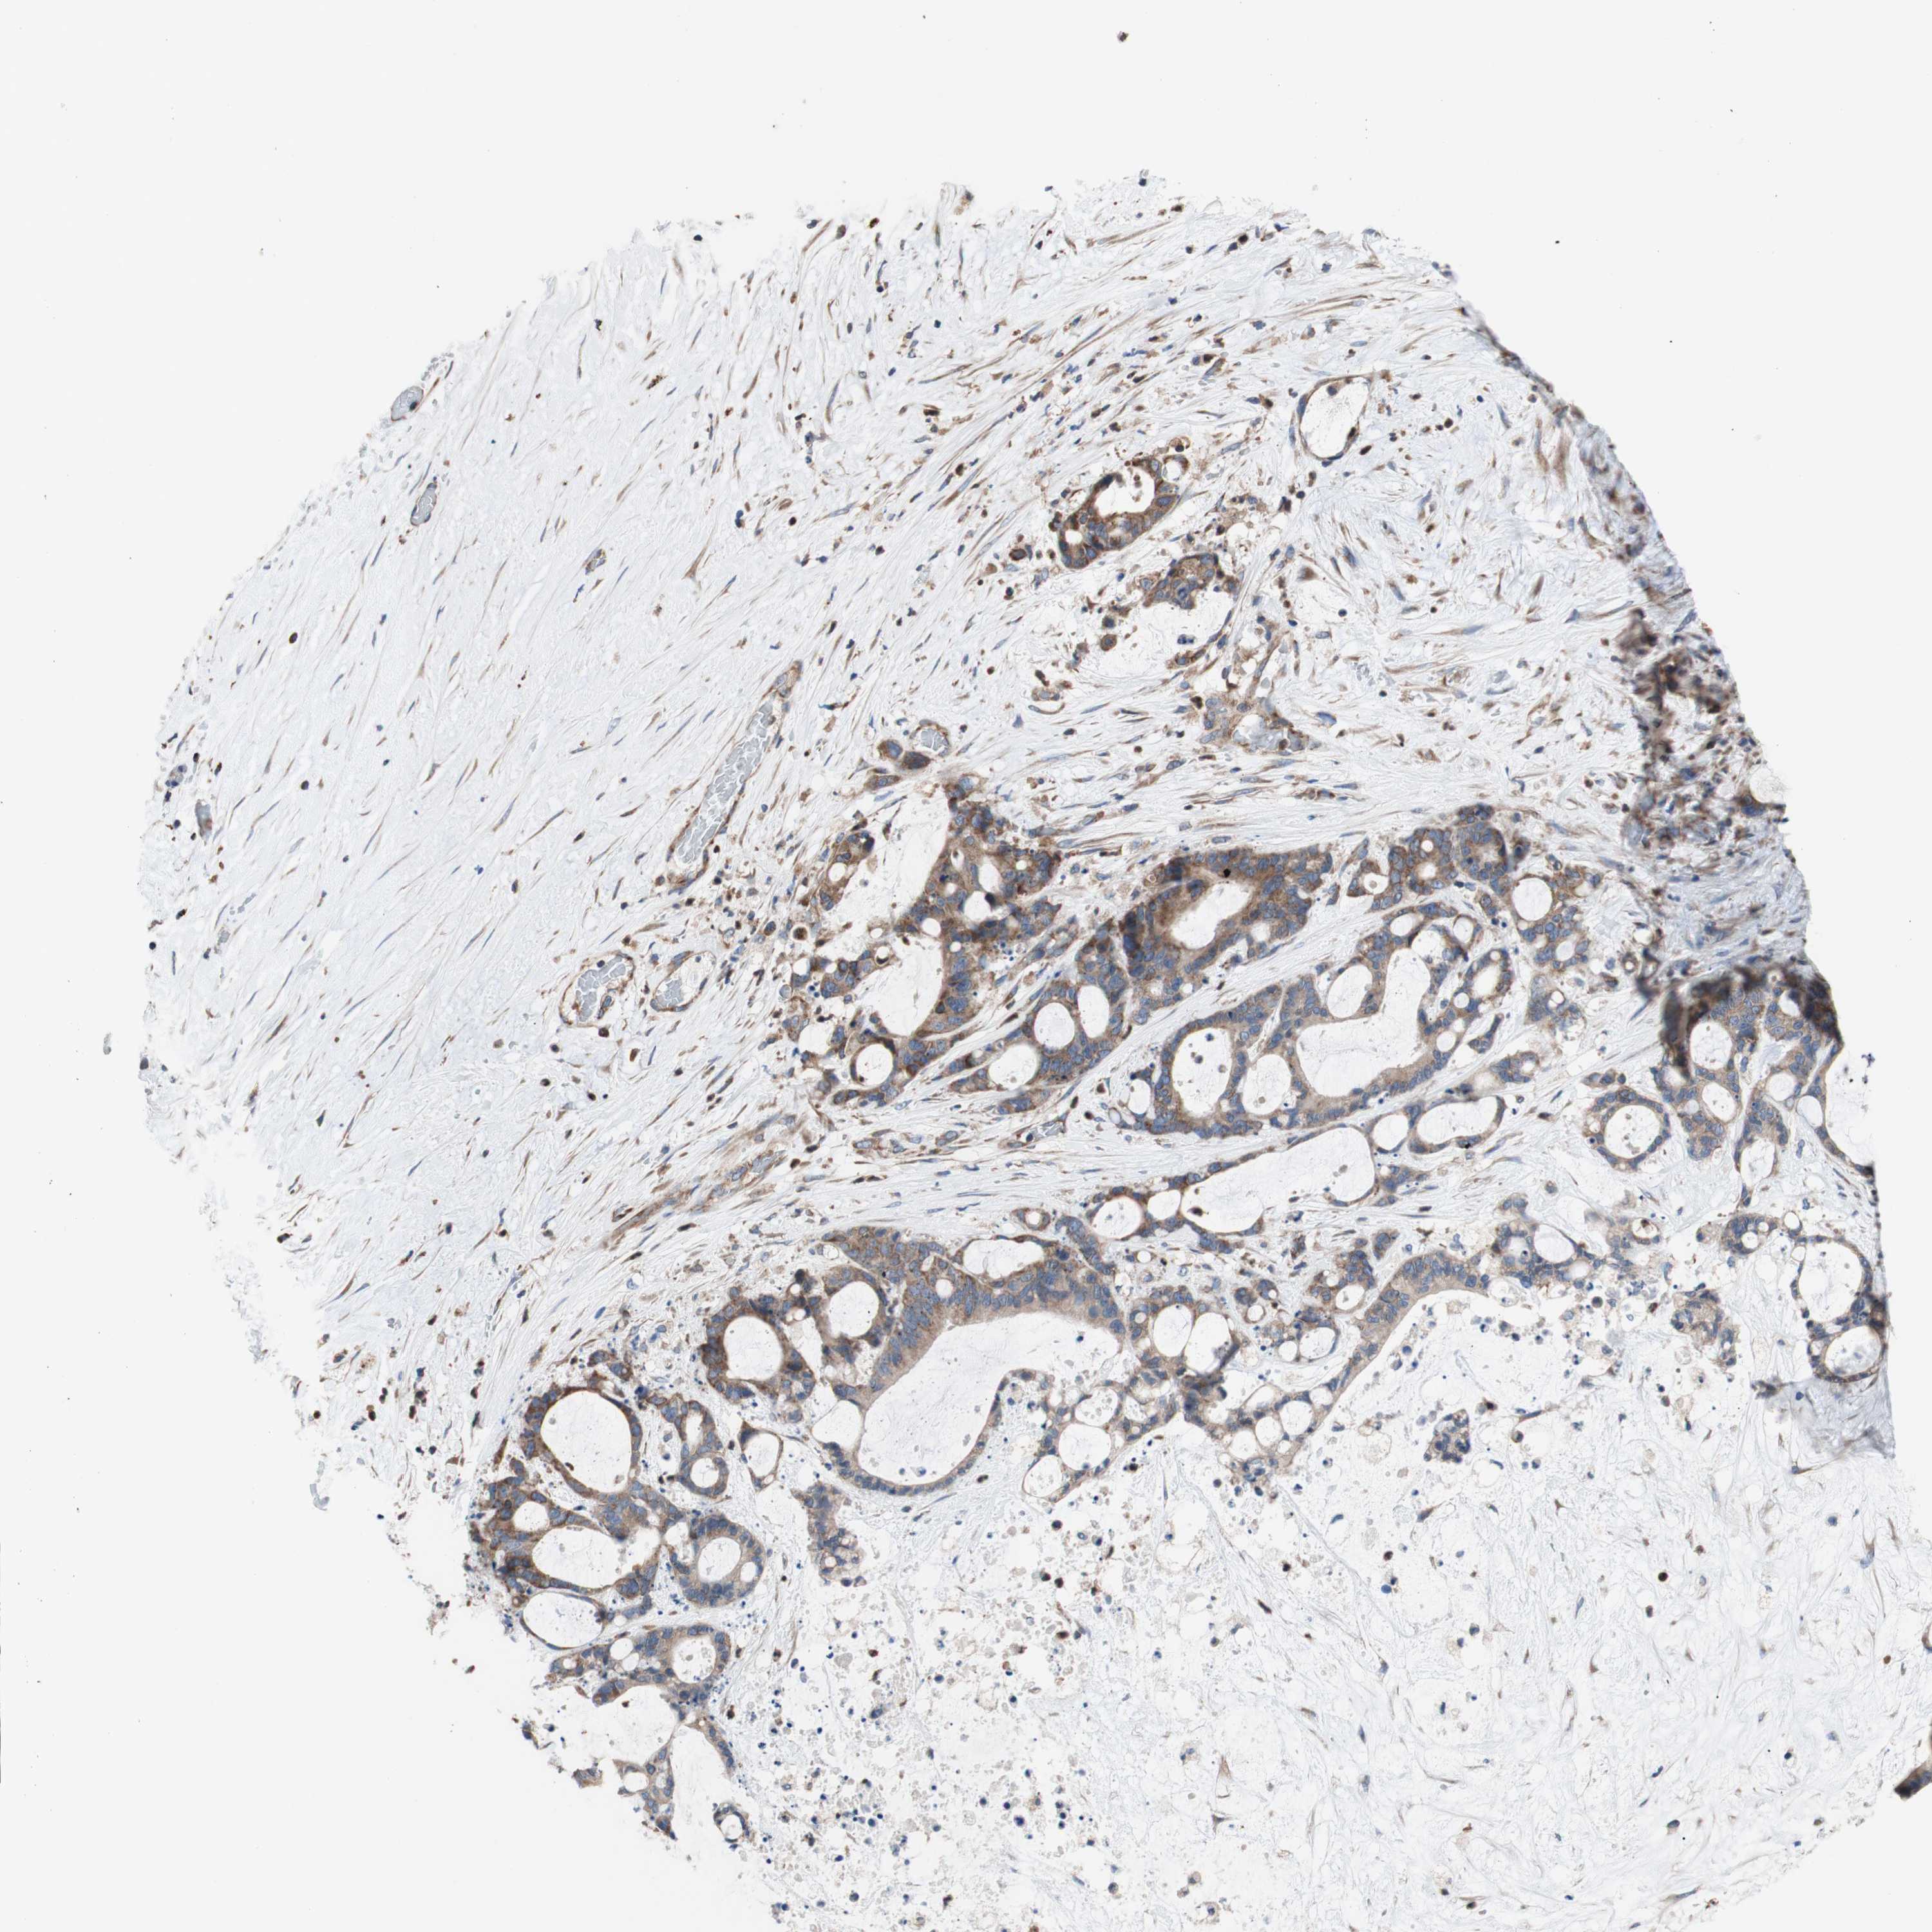

LIVER CANCER - Protein expressioni

A mouse-over function shows sample information and annotation data. Click on an image to view it in a full screen mode. Samples can be filtered based on level of antibody staining by selecting one or several of the following categories: high, medium, low and not detected. The assay and annotation is described here.

Note that samples used for immunohistochemistry by the Human Protein Atlas do not correspond to samples in the TCGA dataset.

Antibody stainingi

Antibody staining in the annotated cell types in the current human tissue is reported as not detected, low, medium, or high, based on conventional immunohistochemistry profiling in selected tissues. This score is based on the combination of the staining intensity and fraction of stained cells.

Each image is clickable and will lead to virtual microscopy that enables deeper exploration of all samples and also displays staining intensity scores, fraction scores and subcellular localization as well as patient and tissue information for each sample.

Antibody HPA050118

Antibody HPA056084

Antibody CAB012444

Staining

High

Medium

Low

Not detected

Intensity

Strong

Moderate

Weak

Negative

Quantity

>75%

75%-25%

<25%

None

Location

Nuclear

Cytoplasmic/membranous

Cytoplasmic/membranous,nuclear

Carcinoma, Hepatocellular, NOS

Cholangiocarcinoma